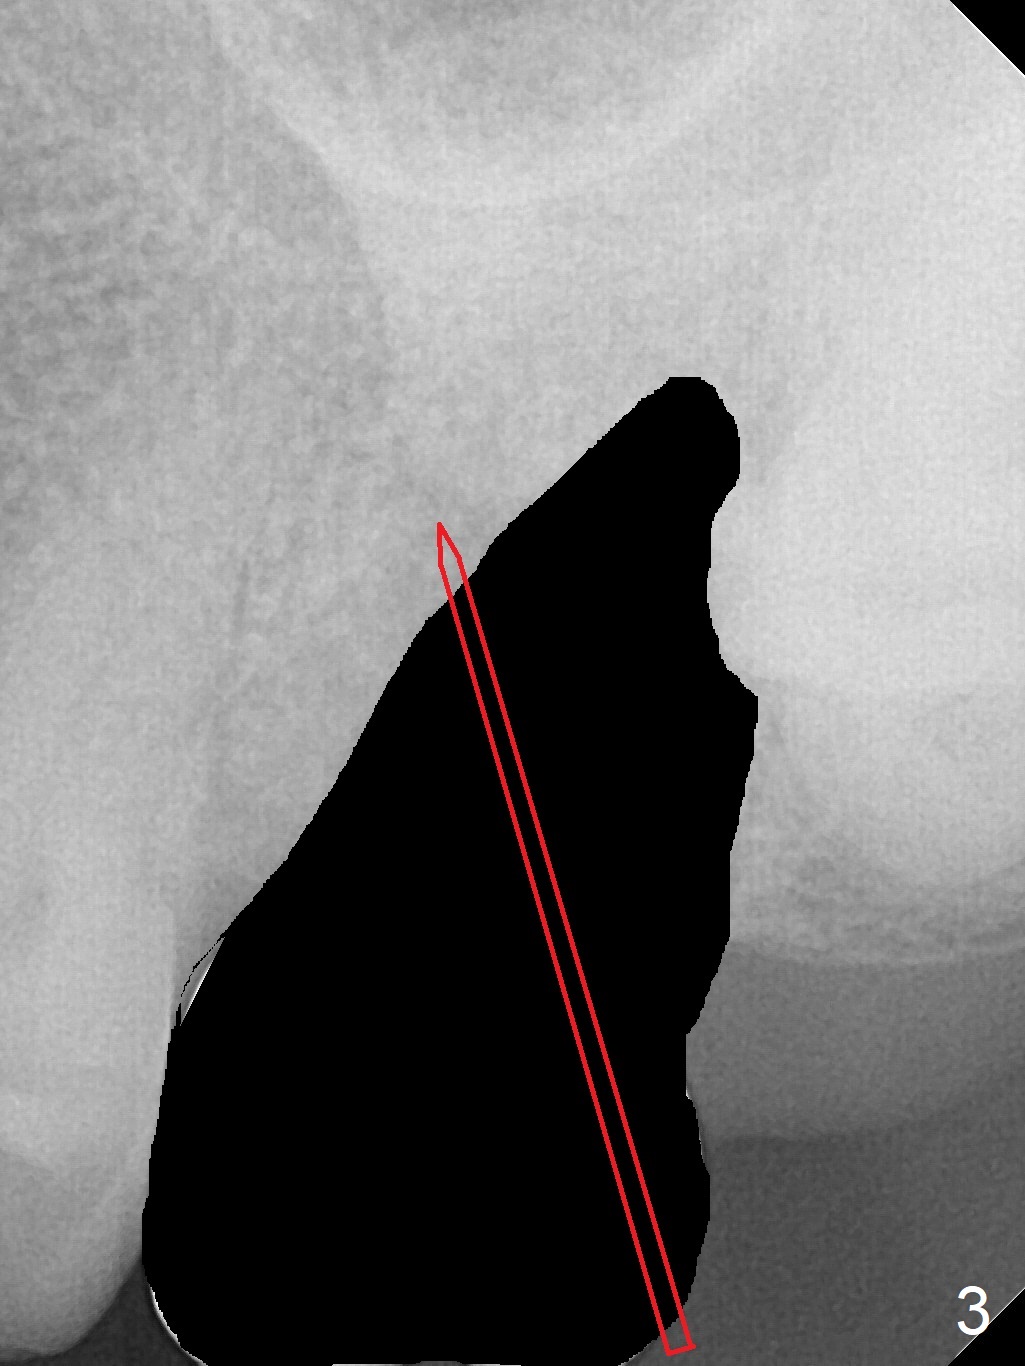

A 64-year-old woman will return for extraction/implant for the upper left 2nd molar with a fistula (Fig.1). Since the roots deviate distal (Fig.2 after extraction), initiate osteotomy in the apical 1/3 of the mesial slope with 1.5 mm drill (Fig.3). Once the lamina dura is penetrated, change trajectory (Fig.4) and extend depth for 15 mm (gingival level). After use of 2 mm drill, insert marked parallel pin for PA. The final implant as well as abutment is shown in Fig.5.